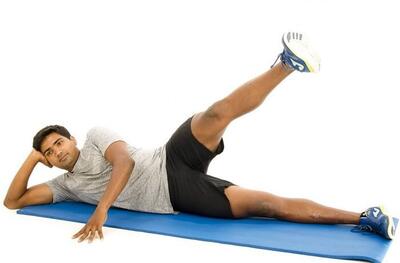

با این حرکت ساده واریس و درد زانو ها را کاهش دهید+ فیلم

بهترین تمرینها برای خداحافظی با زانو درد

درد زانو بسیار شایعتر از آن است که تصور میشود. متخصصان معتقدند ورزش، بهویژه پیلاتس، به سلامت زانوها کمک میکند.

با این تمرینها به سلامت زانوها کمک کنید

حدود ۲۵ درصد بزرگسالان به زانودرد دچارند.